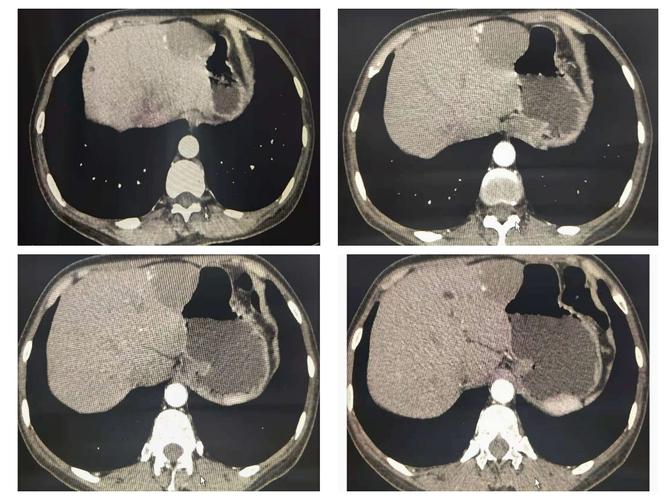

肝血管瘤ct实例分享